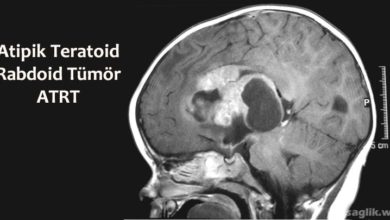

Atipik Teratoid Rabdoid Tümör Nedir? Belirtileri, Tedavisi

Atipik teratoid rabdoid tümör (atypical teratoid rhabdoid tumor, ATRT), birincil merkezi sinir sistemi (MSS) tümörüdür. Bu, beyin veya omurilikte başladığı…